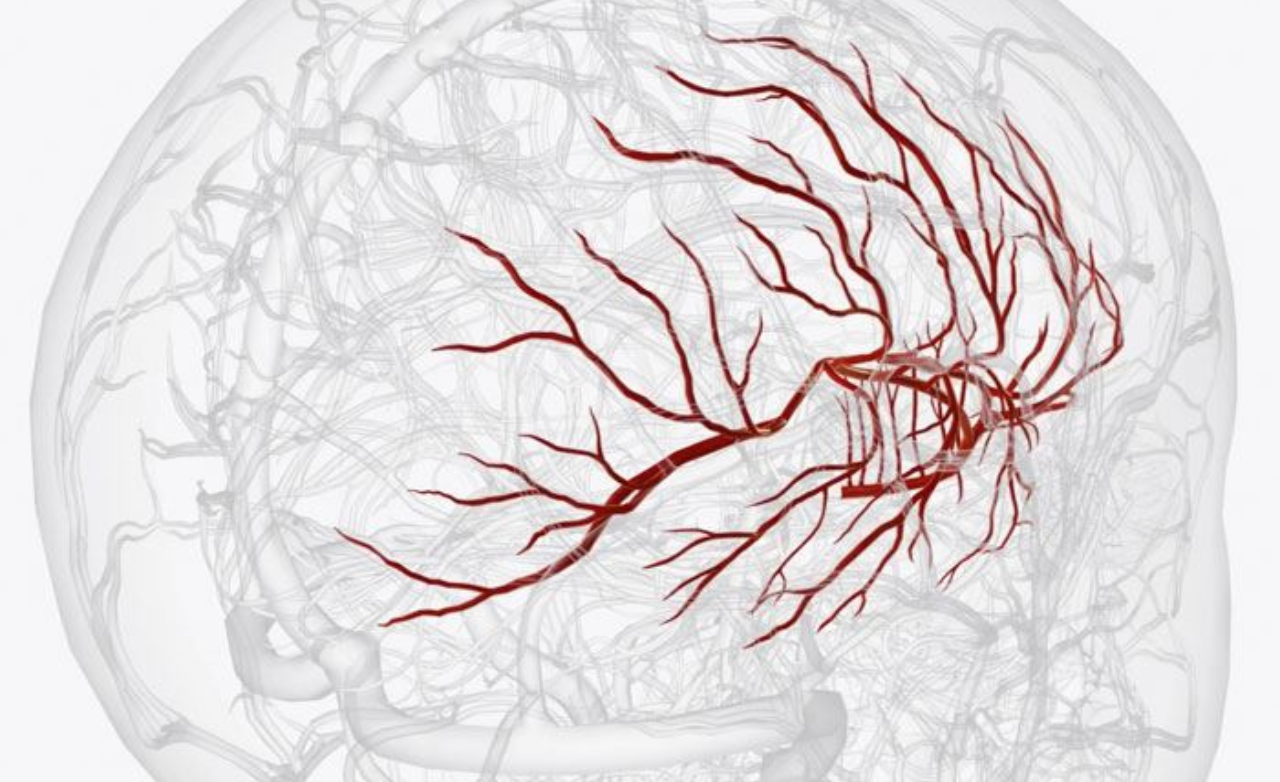

Aneurysm coiling is a minimally invasive procedure used to treat brain aneurysms by preventing rupture. It is performed when weakened blood vessels balloon and pose a serious risk of bleeding.

Using thin catheters, soft coils are placed inside the aneurysm to block blood flow, reduce pressure, and safely prevent future bleeding.